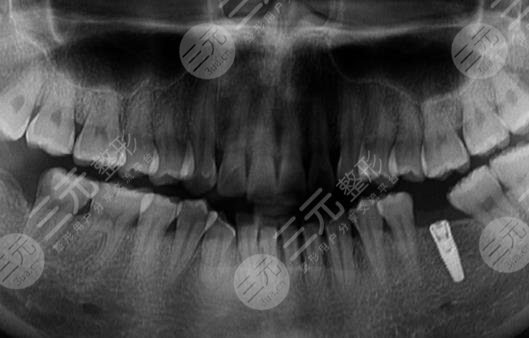

到醫(yī)院進行面診的時候,醫(yī)生先讓我咬了牙齒的模型,然后又拍了牙片,選擇了牙齒的種植體,一星期之后,我來到了醫(yī)院進行種植牙。整個種植牙的過程是很快的,而且因為打了局部mz也沒有任何的感覺。大家現在可以看到我的種植牙是十分成功的,而且看上去十分的潔白,跟周圍的牙齒形成了鮮明的對比。